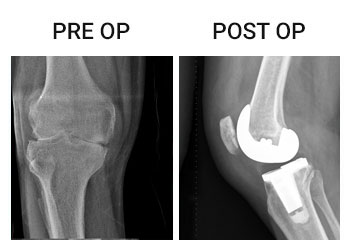

Knee and Hip replacements surgeries are routinely done in this hospital under different categories and Packages. Joint replacement team is headed by Dr.P.Elangovan M.S, Mch Ortho, who has more than 1000 joint replacement surgeries to his credit and is a vastly experienced surgeon and uses both European and American implants. Staggered bilateral knee replacement is the standard practice in this hospital.

• Total Knee Replacement